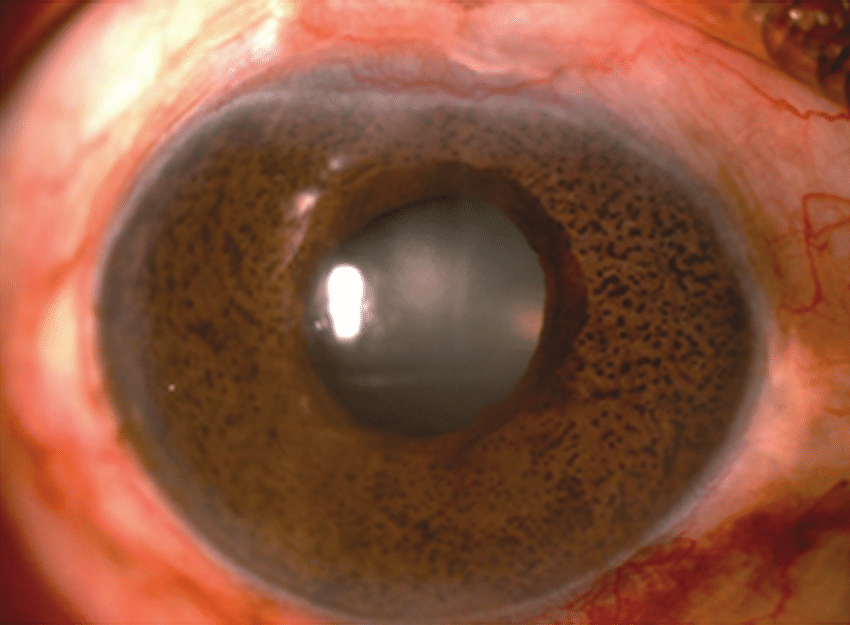

즉, 홍채의 색소결절이 나타나는 것이 가장 큰 특징입니다

홍채의 결절성 변병은 홍채의 실질과 비슷한 구조를 가지며,

항상 세포성 막으로 둘러싸여있는데,

이막은 한층으로된 각막내피세포와 한층의 데스메막을 닮은 막으로 되어있습니다.

즉, 앞서 이야기한 각막내피세포의 비정상적인 증식이 홍채위까지 뻗어있다는 가설을 뒷밤침합니다.

심한경우에는,

광범위한 양상으로 각막 및 홍채의 이상이 동반될수 있는데,

이 경우 수많은 홍채결절(iris dark nodule), 홍채의 겉말림(ectropion uvea), 동공모양이상(pupil distortion)이 발생할수 있습니다.